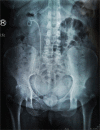

Diagnosis: The kidney ureter bladder (KUB) x-ray showed the presence of a giant stone in the bladder and an entire D-J stent. The computed tomography (CT) urography scans revealed normal left kidney, right hydronephrosis, and an encrusted D-J stent with the significant stone, diameter 4.2 cm with a CT value of 1211.0 ± 221.6 HU, on the vesical coil. On the basis of these auxiliary examinations, the case was diagnosed as cystolith and prolonged-indwelling stents.